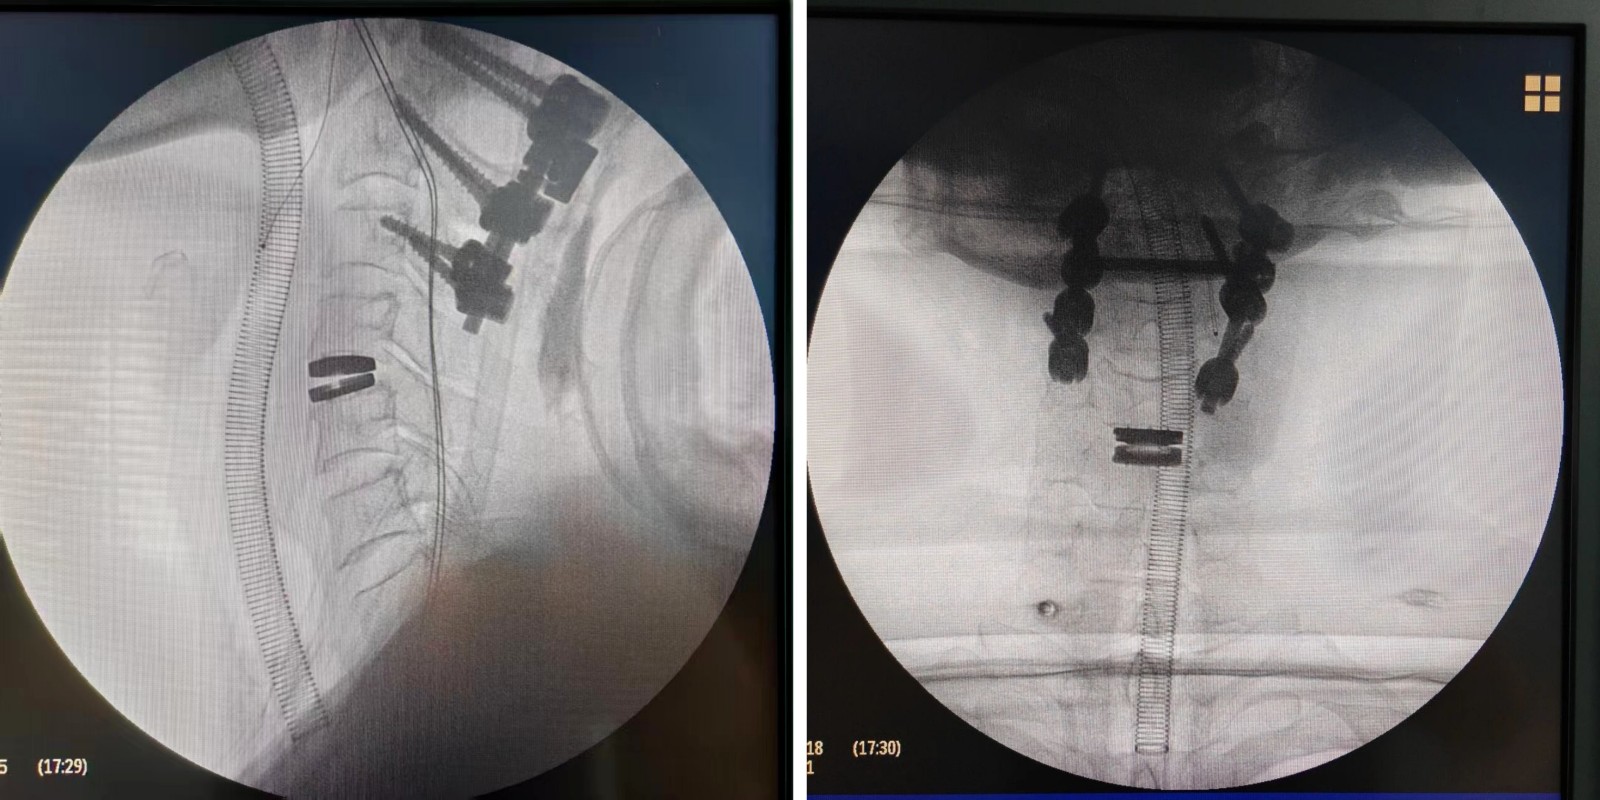

近日,上饶市人民医院骨科吴国保主任团队成功为一名颈椎外伤患者实施“人工颈椎间盘置换术”。该患者因外伤导致枢椎粉碎性骨折伴脱位、颈椎间盘破裂、股骨颈骨折等多发伤入院。经多学科联合评估与周密准备,吴国保主任团队联合麻醉科、重症医学科等专家,先后为一期完成C1、C2、C3切开复位内固定术的患者,顺利开展了二期手术——即上饶市首例人工颈椎间盘置换术。

该手术在保障颈椎即刻稳定的基础上,最大限度保留了患者正常的颈椎活动功能。术中融合精准微创与动态稳定理念,在彻底解除神经压迫的同时,实现颈椎的灵活与稳定兼得,标志着上饶市人民医院在颈椎外科治疗领域迈上新台阶。

颈椎人工间盘置换术其核心目标是在解除神经压迫的同时,更大程度保留颈椎的活动功能。该手术并非更换整节颈椎骨,而是植入可活动的人工椎间盘,替代病变的颈椎间盘。